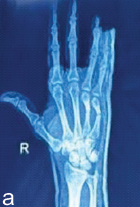

Tubercular Compound Palmar Ganglion Presenting with Chronic Wrist Swelling and Flexor Dysfunction: A Case Report

Nikhil Agrawal , Vaibhav Jain , Harsh Agrawal , Avinash Kumar Upadhyay , Ashutosh Singh Rajavat

………………………………p.267-272